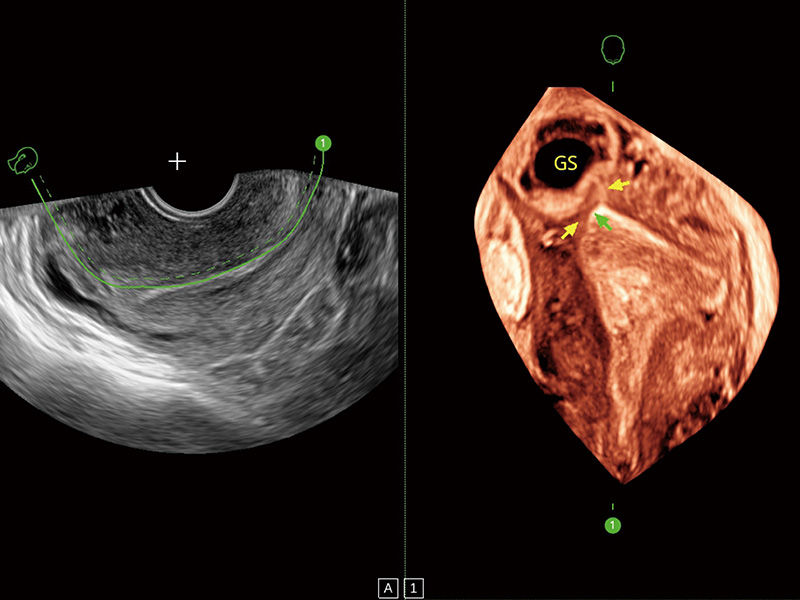

临床图

卵巢多囊样改变